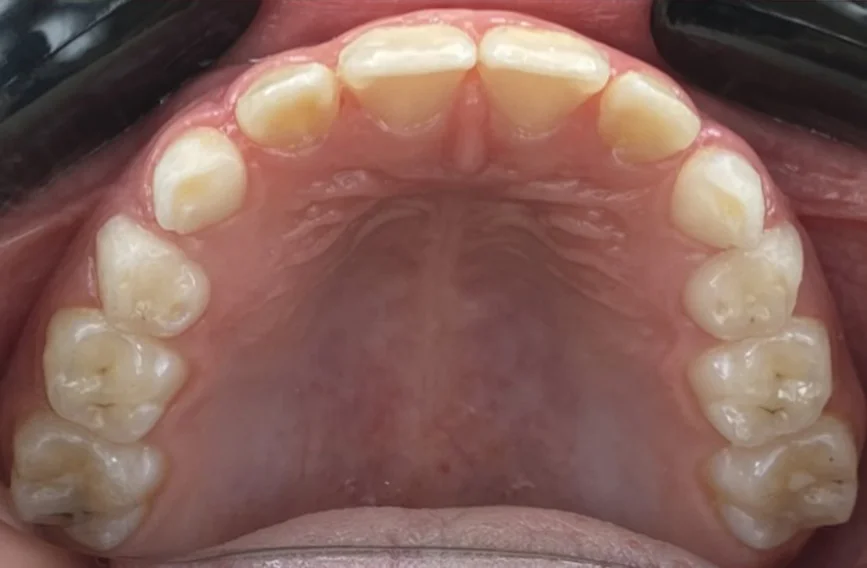

Клинични резултати:

Хармонични зъби дъги с достатъчно място за пробива на постоянните зъби.

Осигуряване на възможност за правилен растеж и съотношение на двете челюсти.

Коригирана е кръстосаната захапка и при усмивка вече се виждат горните фронтални зъби.

Снимки преди и след лечението